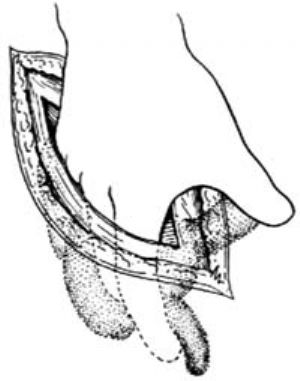

3.當闌尾位於盲腸後,位置固定不易切除時,可切開盲腸外下方的後腹膜[圖3 ⑴],再用紗布包住盲腸向上翻轉,露出闌尾後,作逆行闌尾切除術。另若闌尾較長伴管端粘連固定,不宜按常規勉強提出末端,改爲逆行切除闌尾。先用變止血鉗在靠近闌尾根部處穿過其系膜,帶過兩根4-0號絲線,雙重結紮闌尾根部[圖3 ⑵]。在結紮遠端1cm處夾一把彎止血鉗,用刀在止血鉗與結紮線之間切斷。闌尾殘端消毒處理後,根據具體情況行荷包縫合包埋或褥式縫合包埋。再用彎止血鉗向闌尾尖端方向分段鉗夾、切斷闌尾系膜[圖3 ⑶]最後切除闌尾,一一結紮近端闌尾系膜。

⑵結紮闌尾根部

⑶分段鉗夾、切斷闌尾系膜